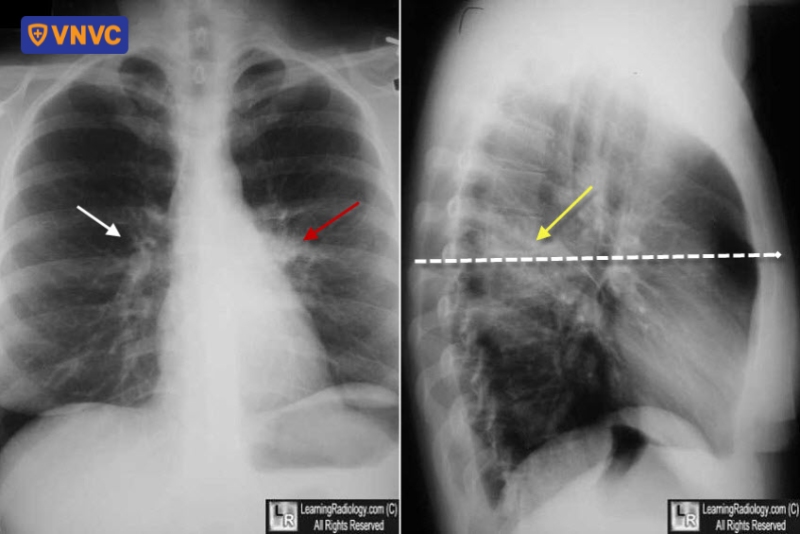

Trên phim chụp X-quang phổi hoặc hình chụp CT, hai rốn phổi sẽ có độ đậm xấp xỉ bằng nhau. Tuy nhiên, trong trường hợp không có vôi hóa phổi (liên quan đến bệnh u hạt trước đó), nếu một rốn phổi “đặc hơn” rốn phổi còn lại, cần nghi ngờ có sự tồn tại của hạch rốn phổi to hoặc khối u: